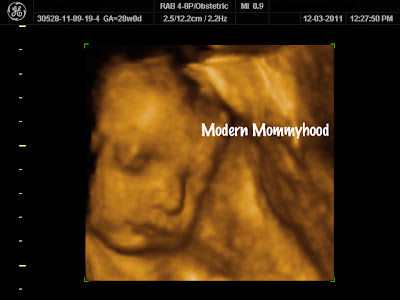

| Look at those little arms and hands! |

| Chubby Cheeks! |